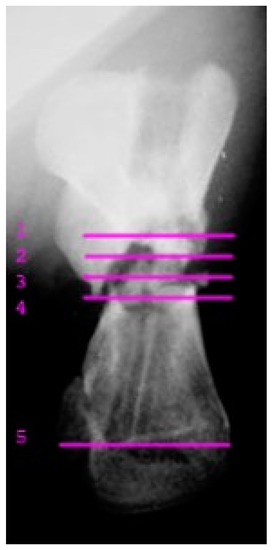

A juvenile sea turtle was presented to the Sea Turtle Clinic (STC) of Veterinary Medicine Department of the University of Bari with an entanglement lesion affecting the right front flipper. On admission, the sea turtle was measured and underwent a complete physical examination; curved carapace length (CCL) from notch to tip ranged 41 cm, curved carapace width (CCW) was 37 cm, and the weight was 18 Kg. The turtle appeared responsive but weak and dehydrated. Clinical evaluation of the musculoskeletal system performed out of the water showed swelling of the right front flipper and evidence of pain on deep palpation of the respective brachial muscle. A reduction in the right front flipper’s range of motion was observed when the turtle was examined in the water. Radiographic assessment, in dorso-ventral (D-V) and Caudo-Cranial (C-C) projections, indicated detachment of the distal epiphysis of the humerus, compatible with a type II Salter-Harris fracture, together with a transverse diaphyseal fracture (Figure 1). The turtle underwent general anesthesia, and the craniodorsal access to the humeral diaphysis was performed. The epiphyseal fracture was reduced by closed surgery and fixed using two crossed 2.5 mm Kirschner pins, introduced backward from the distal stump and brought out through the hyperflexed humerus-radio-ulnar joint. The same pins used to fix the epiphyseal fracture were inserted into the proximal stump to fix the diaphyseal fracture. After checking the stability of the fractures reductions, the surgically sectioned soft tissues were reconstructed, and post-operative radiographs were performed. Follow-up was performed after the surgery at 2, 4, 12, 16, and 24 months, when the turtle was released at sea. Three months after its release at sea, the turtle was caught dead in a fishing net at a depth of 40 m. To determine the evolution of bone repair from turtle release to death, the right humerus was removed for histological and histomorphometry analyses. Immediately after explant, the humerus was fixed in 4% buffered paraformaldehyde, dehydrated in ethanol, and embedded in methylmetacrylate. Serial cross sections, 750 µm thick, were cut at both the diaphyseal and epiphyseal fracture gaps using a circular diamond-bladed saw (Gillings Hamco) and were ground to a thickness of 100 µm. Sections were placed on a specimen holder and microradiographed using a microradiograph (Constant 1-K, Ital Structures, Italy) at a prefixed distance from the X- ray generator of 9.5 cm. X-ray exposure was set up at 8 kV and 14 mA. Contact microradiographs were obtained on Kodak high-resolution film (SO 343, Eastman Kodak Co., Rochester, NY, USA), developed with Kodak HC-110, fixed in Kodak UNIFIX, washed in distilled water and then airdried at room temperature. Sections were subsequently stained with 1% toluidine blue (pH 3.7) for mineralized tissue. Four separate levels were selected, three belonging to the mid-diaphyseal fracture gap, and one level to the epiphyseal fracture gap: the first and the fourth levels corresponded to the proximal and distal part of the callus, respectively, and the second and third levels to the center of the fracture (Figure 2). As a control, the left humerus, which had never been fractured, was processed with the same procedure. On the stained sections, using a Nikon DS-5 camera connected to a stereomicroscope (SMZ800, Nikon Europe B.V., Amstelveen, The Netherlands) and a DS camera control unit, the callus extension was measured and the amount of new laid down bone, cartilage, and fibrous tissue, expressed as percentage ratio of the entire section, were evaluated. Histomorphometry was performed using Nis-Elements BR analysis software (Nikon Europe B.V.).

Figure 1. Caudocranial radiograph of the anterior right flipper showing transverse diaphyseal and the type II Salter-Harris fractures.

Figure 2. X-ray image of the humerus showing the levels from which the histological and morphometric findings and the microradiographs. Numbers 1 to 4 correspond to the first, second, third and fourth diaphyseal level, respectively. Number 5 corresponds to the distal epiphysis level.